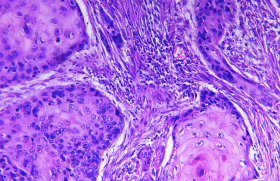

Lésions précancéreuses